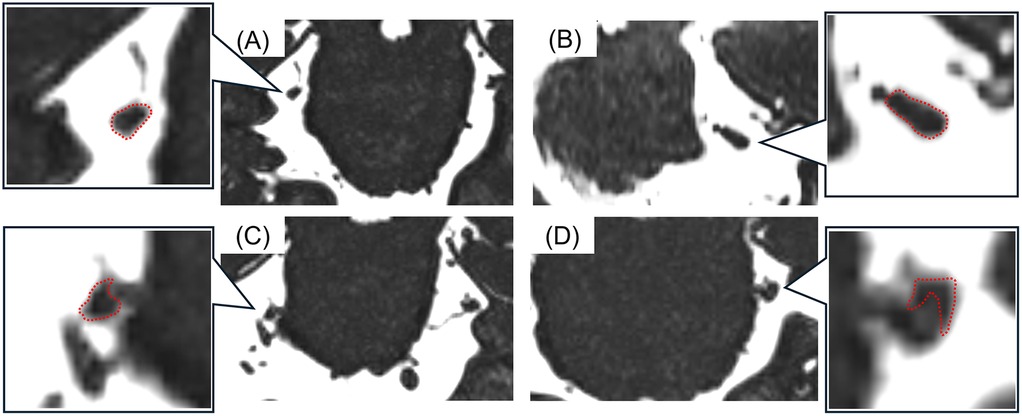

All MR images were obtained at the REZ of the trigeminal nerve by using a three-tesla MRI scanner (Magnetom Spectra, Siemens, Germany) with a 16-channel head coil according to our previous study (15, 26). MR angiography (MRA) was obtained using 3D time-of-flight (3D-TOF) MRA with the following parameters: repetition time/echo time, flip angle = 24/3.9 ms, 18°; field of view 160 mm × 160 mm; matrix 320 × 192; section thickness 0.5 mm; and slab number 3. MR cisternography was obtained using 3D-constructive interference in steady-state (3D-CISS) MRA with the following parameters: repetition time/echo time, flip angle = 7.4/3.7 ms, 50°; field of view 160 mm × 160 mm; matrix 320 × 320. These MR images were reconstructed to a voxel size of 0.5 mm × 0.5 mm × 0.5 mm and slab thickness of 44 mm. All 3D-TOF and 3D-CISS images were displayed in triplanar views (transverse, coronal, and sagittal views) on the visualization system. Images were assessed for NVC presence by two experienced radiology specialists blinded to the laterality of symptoms. NVC presence was defined as contact between the blood vessel and the trigeminal nerve at REZ. When cerebrospinal fluid was not present between them in the 3D-CISS, it was defined as “with NVC” (Figure 2). In case of disagreements or uncertainties, whether there was contact or not, it is regarded as “without NVC”. Regarding details of NVC, the blood vessels involved in NVC and the degree of NVC, whether with only simple contact or with compression or displacement, were assessed (Figure 3).

Figure 3

Images of brain MRI with A, B, C, and D panels. Each presents insets magnifying specific regions highlighted with red dotted lines.

Figure 3. The images of detailed neurovascular compression (NVC). (A) Without NVC, (B) contact, (C) compression, (D) displacement. The detailed NVC conditions were assessed according to the shapes and courses of the trigeminal nerves (surrounded with a red dotted line).